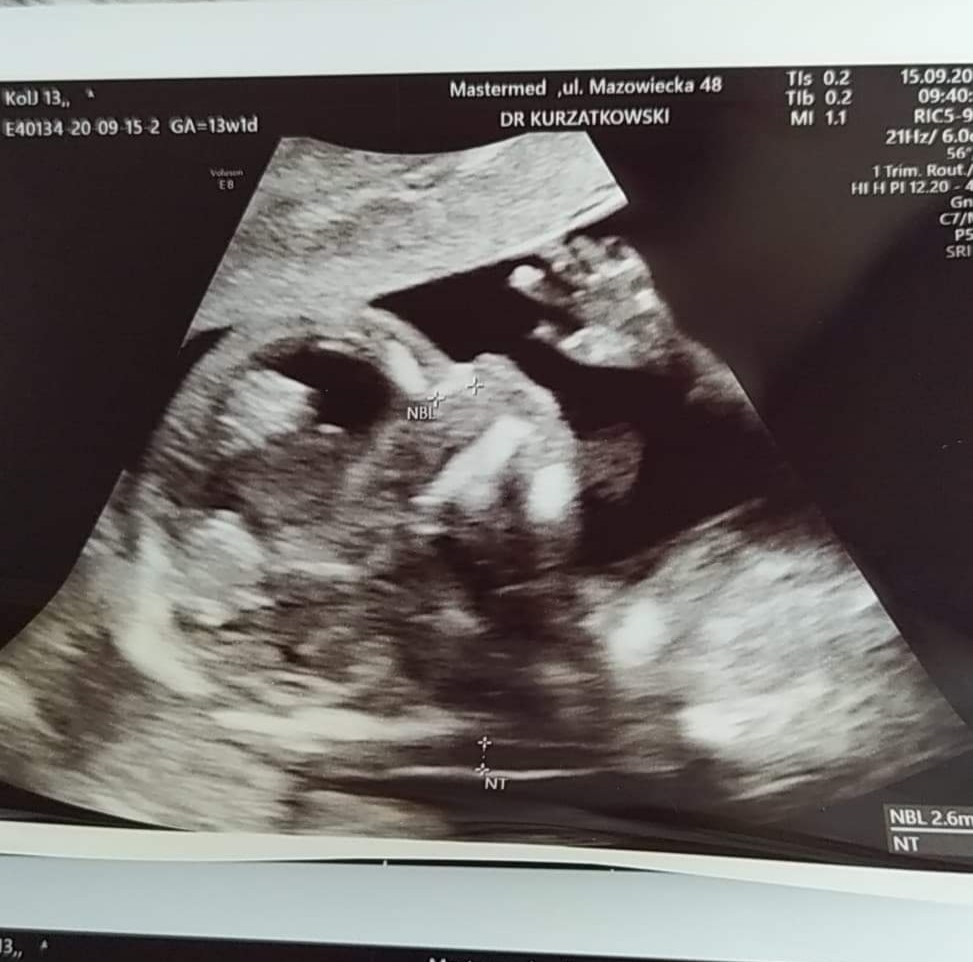

Mi wczoraj z USG też wyszło 19 marzecU maleństwa wszystko dobrze. Ma 7,15 cm. Data porodu z USG 19 marca. Lekarz przyczepił się do mojej wagi, że nie mógł wszystkiego zobaczyć przez brzuch. Ale w opisie jest że płód jest nisko nad kośćmi spojenia.

Nie pokazał co ma między nogami ale ładnie pomachałZobacz załącznik 1176496